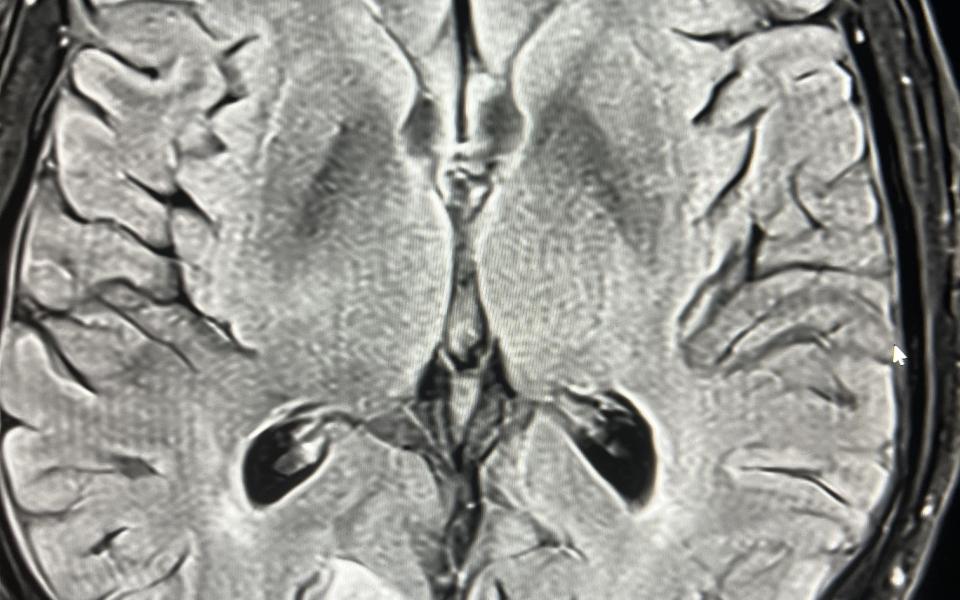

A 77 male presented with a 10 history of visual symptoms following heavy exertion. He described it as an afterimage on his left temporal field eg he would see a person walking past and then see them